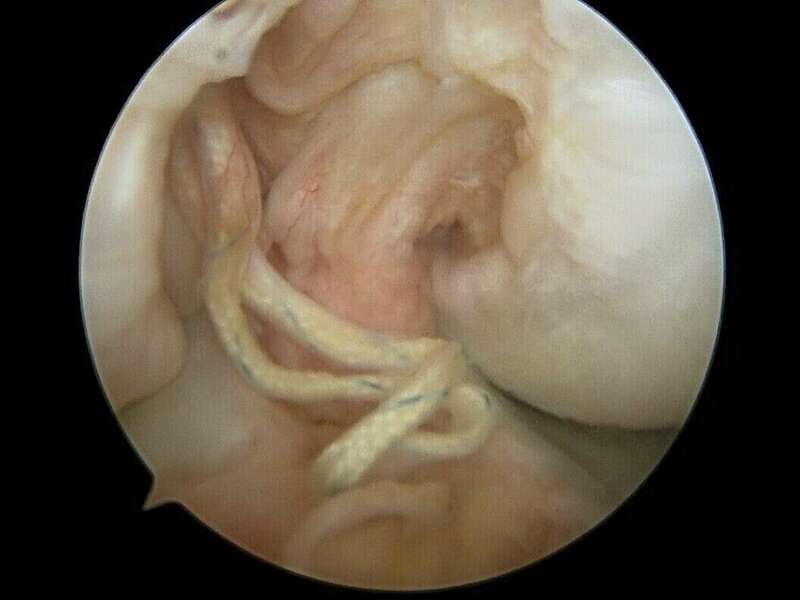

Galerie photo